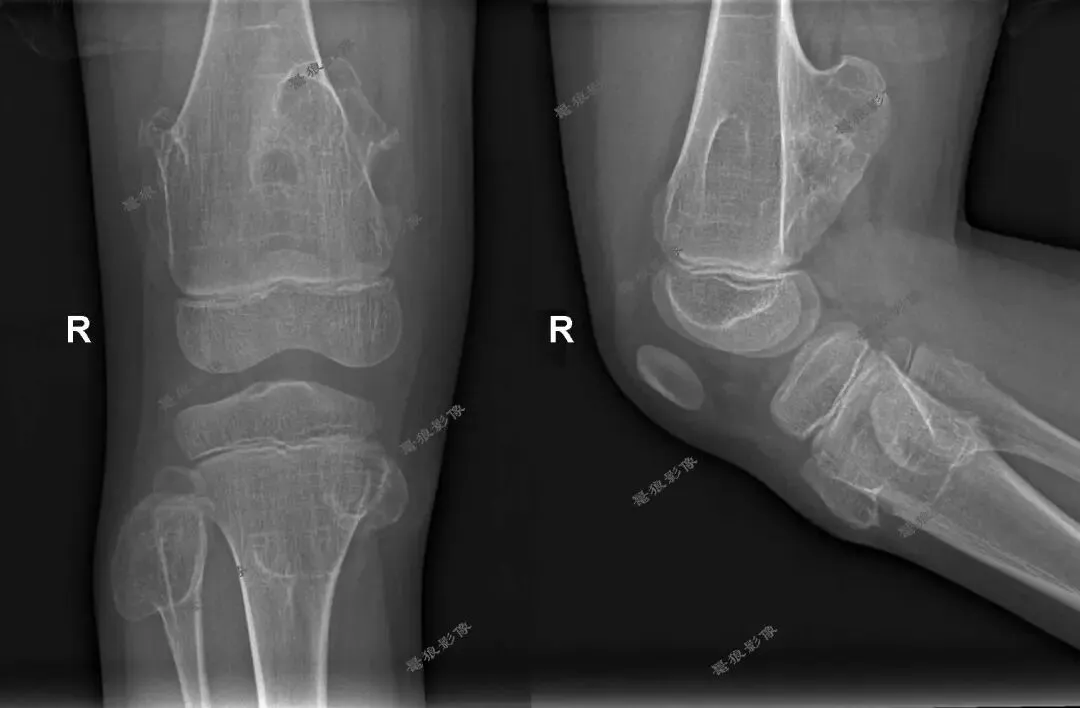

M,7y。双腕及双膝周围多处隆起就诊。

双腕关节及双膝关节X线片如下图:

考虑双腕关节及双膝关节旁多发骨软骨瘤,右膝为甚。